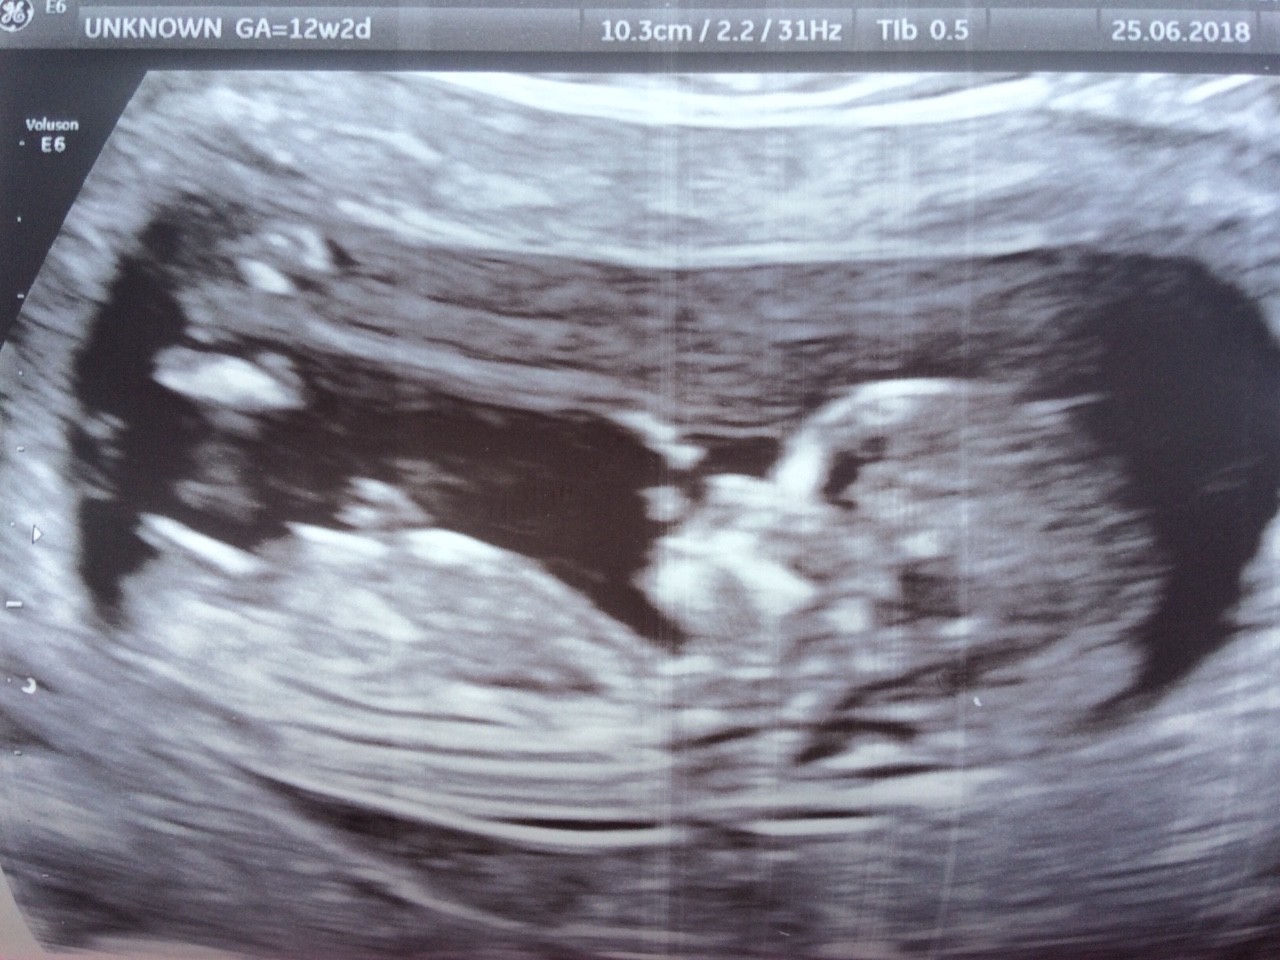

Nie nie nie, tzn. tak w kwestii 16 tyg, ale nam lekarz pokazywał i tłumaczył na podstawie tego wyrostka, to taka kreska widoczna na usg. I mówił, że jak jest w poziomie, to dziewczynka, a jak sterczy ku gorze, chłopiec. Zobacz załącznik 877383

U mnie wyraźnie widać w poziomie. To zdjęcie z prenatalnych. Więc by się zgadzało.

O jakiej kresce mówicie? Bo nie wiem.na co patrzeć ;)